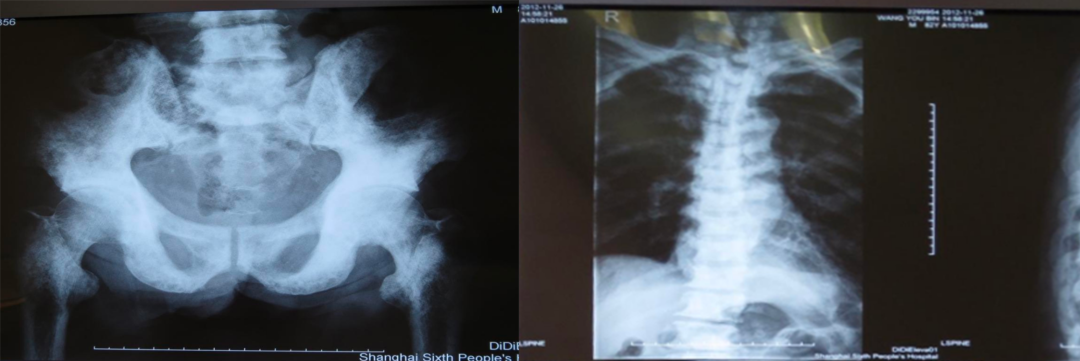

二、骨质疏松症如何进行影像学检查

X线平片是检出脆性骨折,特别是胸、腰椎压缩性骨折的首选方法。常规胸、腰椎X线侧位摄片的范围应分别包括胸4至腰1和胸12至腰5椎体,基于胸、腰椎侧位X线影像并采用Genant目视半定量判定方法,椎体压缩性骨折的程度分类如下:

实验室检查:BMD(L1-4 T值 4.7、SDNECK T值 0.1SD)。

诊断:前列腺癌、骨转移。